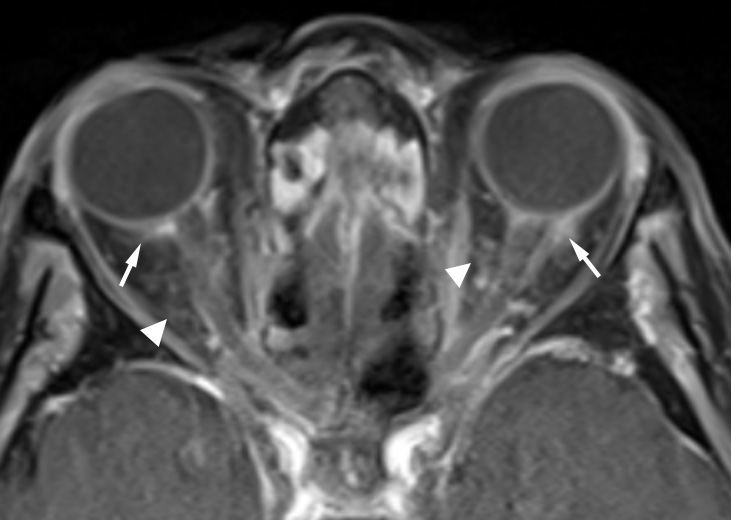

Three weeks later, oral prednisone had been discontinued and the patient began developing new ocular symptoms in her left eye as well as a right 3rd nerve palsy. C-ANCA positivity was confirmed. Despite high-dose steroids, the patient progressed to NLP vision in the contralateral left eye, and repeated MRI demonstrated interval development of acute left optic nerve ischemia and bilateral intra-orbital inflammation (Figure 1 [Fig. 1]). Repeat ENT biopsy was obtained and demonstrated focal arteritis with some giant cells and no invasive fungal elements, ruling out invasive aspergillosis and confirming the suspicion of GPA. The patient developed a nasal deformity with a saddle nose, cotton wool spots in the left retina, and acute renal failure requiring dialysis. Reinstitution of high-dose steroids and adjunctive cyclophosphamide reversed the patient’s acute renal failure and the 3rd nerve palsy, but did not reverse her vision loss.

Figure 1: Post-Gd axial T1-weighted MR image with fat saturation shows enhancement of bilateral posterior sclera extending to the adjacent optic nerve sheath (arrows); findings are consistent with scleritis. Also noted is mild ill-defined enhancement in retro-conal fat (arrowheads), consistent with mild post-septal cellulitis.